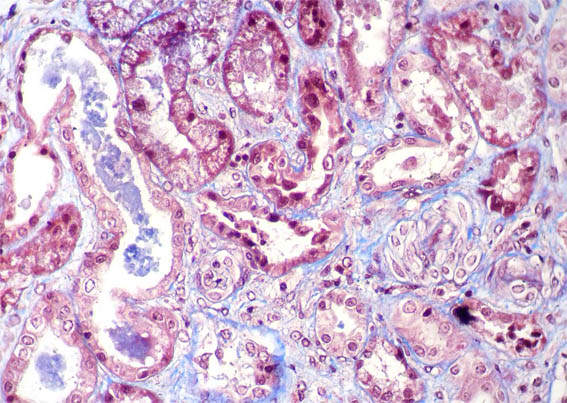

Figure 8. Masson's trichrome, X400.